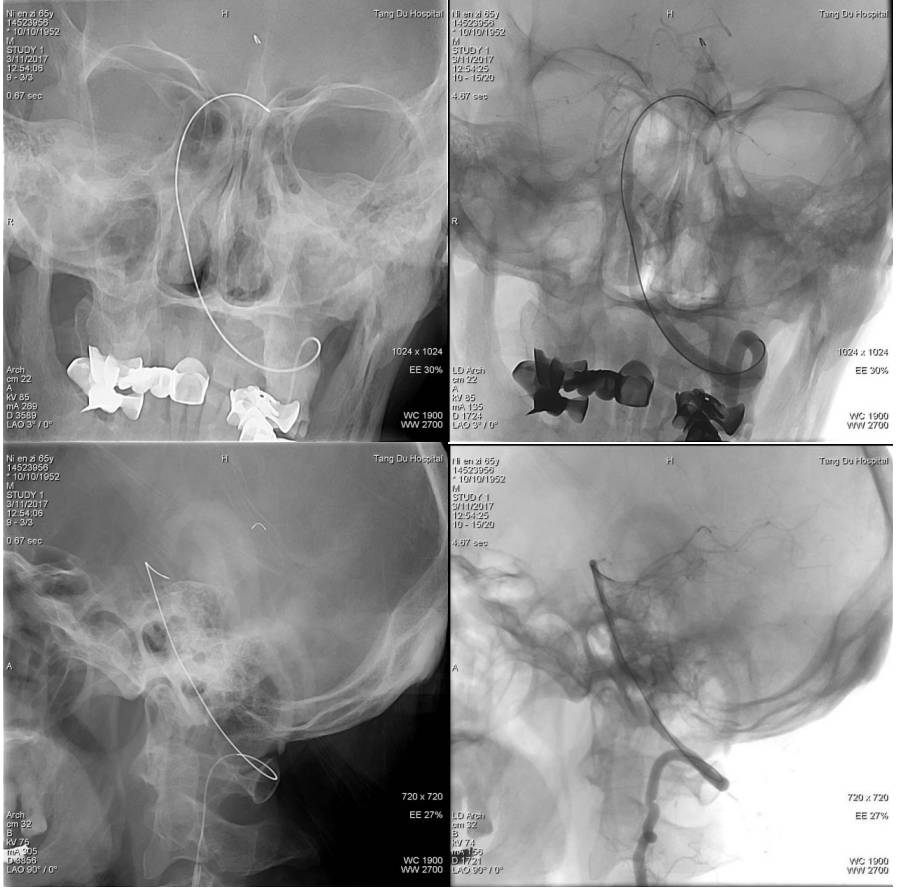

完善相关检查后,急诊行全脑血管造影术

示右侧大脑后动脉P1段不显影,右侧后交通动脉开放。左侧P1中段闭塞,左侧前循环无明显代偿。考虑该血管为责任血管,急诊行血管开通术。

术中用微导管将支架放置狭窄部位,术中见支架Mark显影良好,释放支架5分钟,回收支架,可见支架上附着血栓。

行血管造影示:双侧大脑后动脉显影,远端血管快速充盈,TICI:3级,术毕。患者言语较前流利,可准确应答,左侧肌力恢复正常,NHISS评分1分。

术前脑血管造影显示左侧大脑中动脉急性闭塞,代偿不佳

微导管通过血栓后造影显示远端血管通畅

使用ReviveSE取栓,一次成功